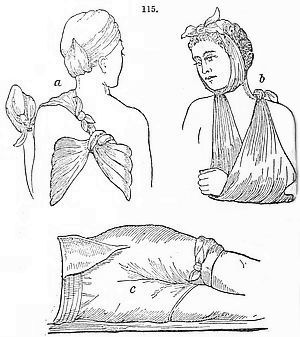

The Sickroom.—The Room; the Nurse; the Bed; Sickroom Accessories; Feeding Patients; Invalid Dishes and Drinks; Administering Physic; Domestic Remedies; Accidents and Emergencies; Bandaging; Burns; Carrying Injured Persons; Wounds; Drowning; Fits; Frostbites; Poisons and Antidotes; Sunstroke; Common Complaints; Disinfection, &c.